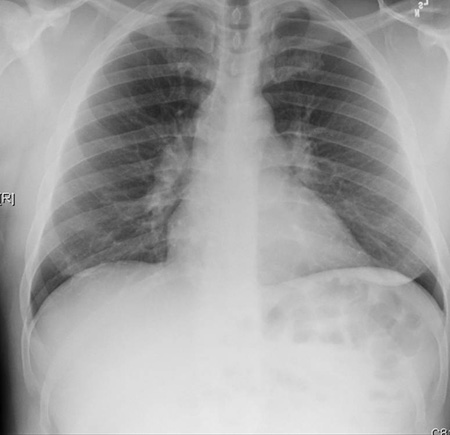

Radiografia torácica

Uma radiografia torácica deve ser obtida no início da avaliação da tosse crônica.[38] Embora não seja diagnóstica das causas mais comuns, os achados podem facilmente desviar a avaliação para causas de maior gravidade como doenças pulmonares estruturais. Eles incluem câncer pulmonar, fibrose pulmonar, tuberculose, bronquiectasia, pneumonia, aspiração e sarcoidose.[Figure caption and citation for the preceding image starts]: Radiografia torácica mostrando hiperinsuflação em paciente com DPOC. A hiperinsuflação é causada pelo componente de enfisema na DPOC, em vez da bronquite crônica subjacente aos sintomas da tosseDo acervo pessoal do Dr. M. A. Sharifabadand, SUNY na Stony Brook School of Medicine, Departamento de Medicina Pulmonar e Intensiva, Mineola, Nova York, e Dr. J. P. Parsons, The Ohio State University Medical Center, Columbus; usado com permissão [Citation ends].